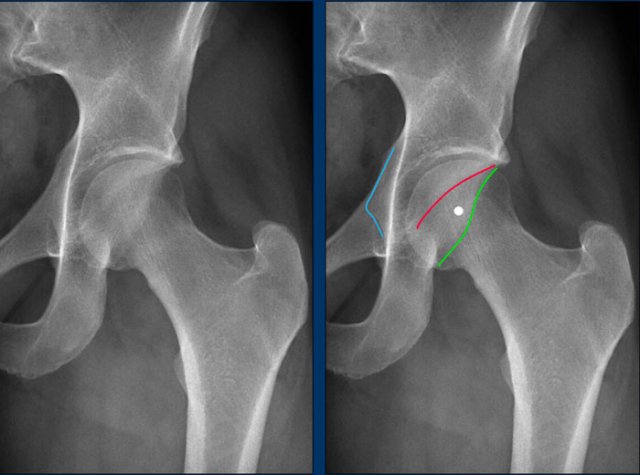

This is a detail of an AP Pelvis X-ray.

First study the image.

Then scroll to the next image.

Findings

• Cross-over sign - the superior portion of the anterior acetabular wall (red line) extends laterally beyond the posterior acetabular wall.

• Posterior wall sign - the posterior wall projects medially to the center of the femoral head.

• Ischial spine sign -  the ischial spine projects more medially than normal (blue line).

These findings are consistent with acetabular retroversion, leading to a global pincer morphology.

Notice that there is also some cam-morphology.

This is another example of pincer morphology.

There is a subtle cross over sign.

In addition there is a posterior wall sign and ischial spine sign.

Notice that there is also cam-morphology (yellow line).